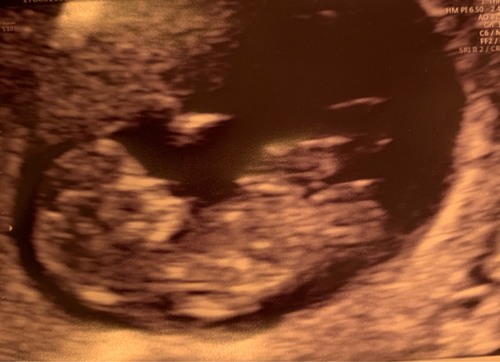

Hierbij nog een foto.. Weet alleen niet of je hier iets kan uithalen. Foto is van 14+2

Vandaag een tussenecho gehad, als overbrugging naar de geslachtsecho op 13 maart. Het is een long shot… (en de baby ligt ook nog eens op z’n kop), maar kan iemand hier wijs uit worden? :-)

Alle foto's bij elkaar denk ik 💗